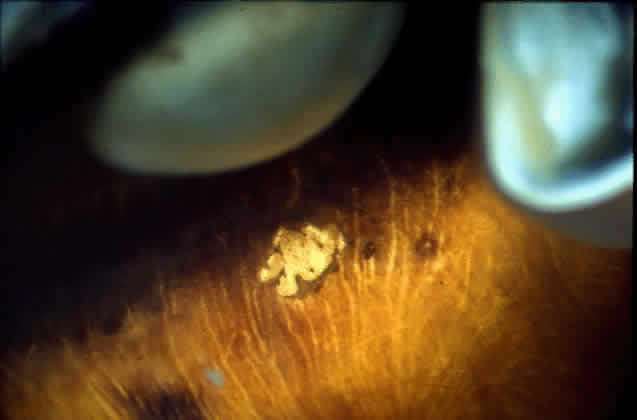

The funduscopic appearance of ischemic lesions in the choroid has been recognized since the early 19th century. In 1904, Elschnig67 described areas of circumscribed secondary RPE loss (Elschnig's spots), which are now recognized to be signs of ischemic infarcts arising from acute occlusion of the choriocapillaris or precapillary choroidal arterioles (Figs. 32, 33, and 34). Multifocal acute ischemic choroidopathy results from acute ischemic lesions of small choroidal arterioles, whereas geographic choroidopathy is due to an occlusion of larger choroidal arterioles or small arteries.47Triangular or wedge-shaped choroidal lesions appear to be three-sided, the apex pointing posteriorly and the base anteriorly. They are believed to represent evidence of occlusion of larger choroidal vessels. Occlusion of the long or short posterior ciliary arteries or their branches results in triangular defects. Triangular defects caused by obstruction of the short posterior ciliary arteries are more numerous, more irregular, and usually smaller. If the triangles become confluent, they may produce hemiatrophy of a quadrant.47,68

Fig. 32. Area of peripheral choroidal ischemia in gross specimen.

Fig. 33. Photomicrograph of area corresponding to that in Figure 31 shows ischemic atrophy of outer retina and retinal pigment epithelium. (H & E, × 25)